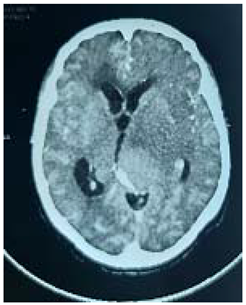

#Case 5:

70 years man, known case of GBM, presented to neurosurgery emergency unit with history of defective speech and progressing Rt side weakness.

We talk to the family and explained the prognosis of the disease,

Operation: through re opening of the previous bone flap, the tumor was invading the dura, adequate macroscopic debulking was made.

Patient was taken to the ICU with oxygen mask, recovered well, showed insignificant improvement in his speech but no change in his weakness,

Histopathology

not obtained.